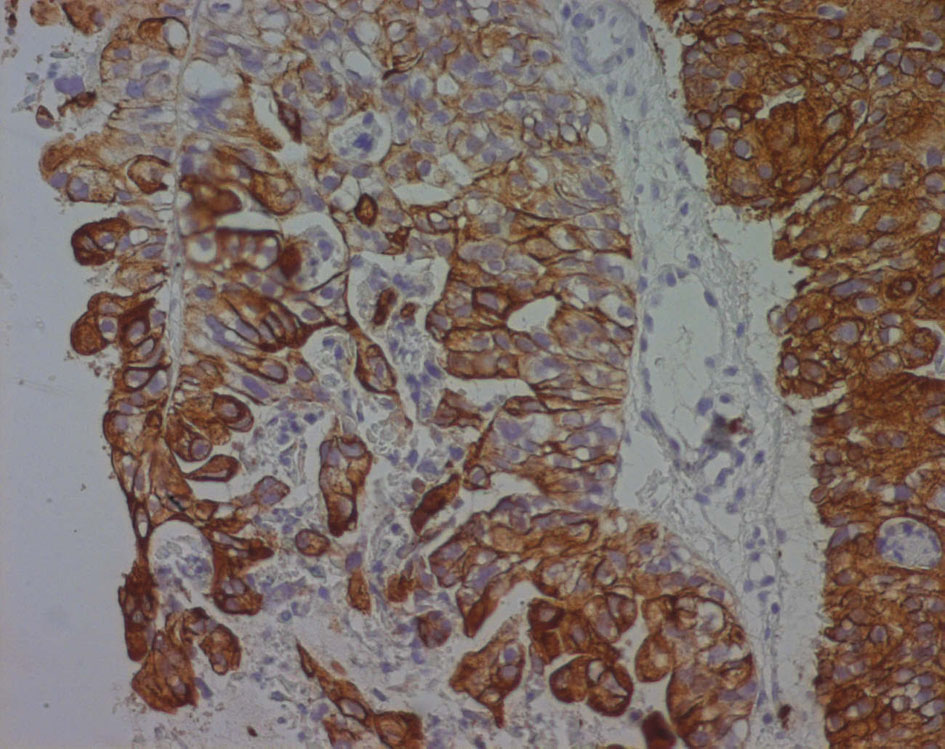

Immunohistochemical evaluation demonstrated that cytokeratin (CK) 7 was positive while CEA, CK20, PSA, CA125 and chromogranin were negative (Fig. 6).

![]() Click for large image | Figure 6. Cytokeratin 7 immunoreactivity in a poorly differentiated seminal vesicle adenocarcinoma. The immunoreactivity appears as a strong brownish cytoplasmic staining in neoplastic cells. |

Immunohistological analysis is strongly suggestive of adenocarcinoma of the seminal vesicle.

Specific immunohistochemical markers would be helpful in this difficult diagnosis because the seminal vesicle may be invaded by tumors of adjacent organs, particularly those of the prostatic adenocarcinoma. In fact, the diagnostic criteria for seminal vesicle adenocarcinoma were modified by Benson et al [5] and the seminal vesicle should be verified macroscopically and microscopically to confirm this diagnosis. Moreover, to confirm that the tumor is completely or essentially localized to the seminal vesicles, PSA, prostate-specific acid phosphatase (PAP), and CEA should be negative. However, increased serum CEA levels can also be observed in rare cases of seminal vesicle adenocarcinoma [6]. Absence of staining of PSA and PAP helps to distinguish seminal vesical adenocarcinoma from prostatic adenocarcinoma [7]. The other differential diagnoses are tumors of other organs adjacent to the seminal vesicles, specifically bladder transitional cell carcinoma (TCC) and rectal adenocarcinoma. Immunohistochemical stains using monoclonal antibodies directed against CK subsets 7 and 20 have demonstrated specificity for bladder TCC and rectal adenocarcinoma [3], as bladder TCC is CK7 and CK20 positive, whereas rectal adenocarcinoma demonstrates only CK20 immunoreactivity. However, only CK7 and CA125 are positive in cases of seminal vesical adenocarcinoma and CK20 is always negative [7, 8] (Table 1), in our case only CK7 was positive and all other biomarkers were negative.